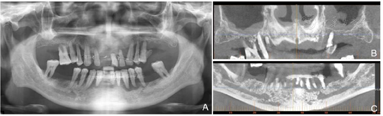

患者口腔卫生差,恒牙列,11、17、26、27、36、41、46、47缺失,11、41见树脂牙修复,牙冠形态不规则,11与21、22、23、12、13间,41与42、43、31、32间可见树脂与金属结扎丝连接固定,树脂连接体部分折裂,边缘见明显悬突。上下颌余留牙齿舌侧见大量牙石,全口牙龈萎缩,牙根暴露约1/3,牙龈局部红肿明显,探诊出血。全口余留牙齿松动Ⅲ度。口腔黏膜检查未见明显异常(图1)。

通过病史及口腔专科检查、X线影像检查,根据2018年牙周病国际新分类标准诊断为Ⅳ期C级牙周炎。